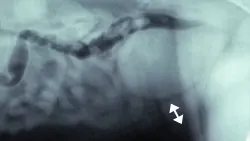

Subsequent coagulation test results were normal. The hemorrhage was attributed to laceration of the caudal epigastric artery at the site of the cystocentesis needle stick, which could have been prevented by simply releasing the syringe when the dog moved and tightened his abdominal muscles during the procedure. The illustration shows the contusion and a lateral abdominal radiograph shows a thickened ventral caudal abdominal wall at the site of hemorrhage (arrow).